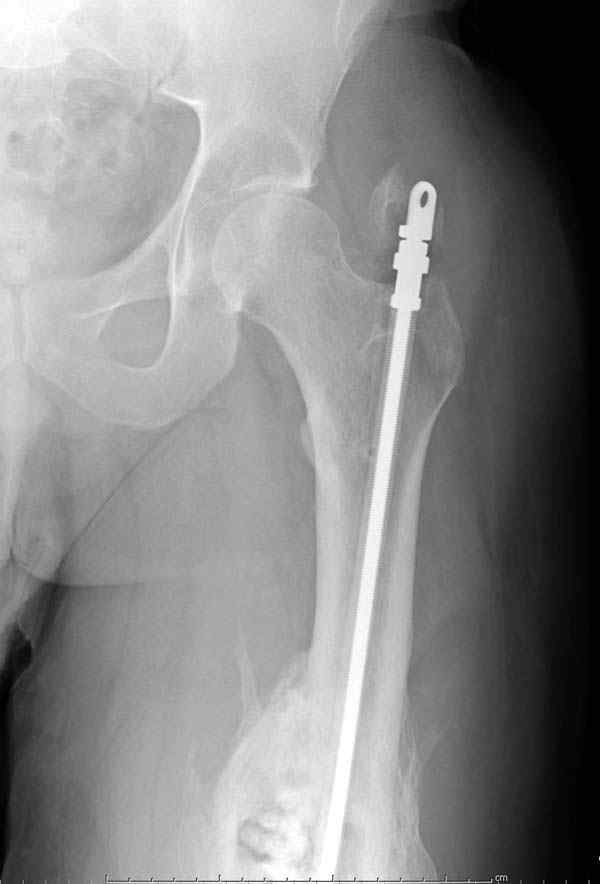

После нескольких некрэктомий, проведения аутодермопластики и заживдения ожоговой раны через 2 месяца после травмы произведен открытый остеосинтез левой бедренной кости штифтом и пластиной (деротационной) [image 01, 02]. Через 1 год и 7 месяцев после травмы у больного диагностированы ложный сустав и хронический остеомиелит левой бедренной кости. Произведено удаление металлических фиксаторов, секвестрэктомия и остеосинтез бедренной костивнешним двухплоскостным стержневым аппаратом [image 03, 04] .

Через 3 года после травмы констатировало отсутствие консолидации бедренной кости, сохранение признаков хронического остеомиелита (свищ в нижней трети левого бедра). Произведен демонтаж аппарата, реостеосинтез бедренной кости спице-стержневым аппаратом, некрсеквестрэктомия. В аппарате удалось лишь частично произвестиустранение углообразной деформации бедренной кости [image 05] .